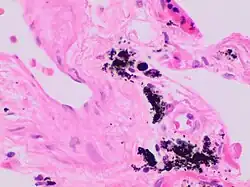

Gandy–Gamna nodules or Gandy-Gamna bodies, sometimes known as Gamna-Gandy bodies or Gamna-Gandy nodules, are small yellow-brown, brown, or rust-colored foci found in the spleen in patients with splenomegaly due to portal hypertension,[1] as well as sickle cell disease. They consist of fibrous tissue with haemosiderin and calcium deposits, and probably form due to scarring at sites of small perivascular haemorrhages.[2] They are visible on MRI scanning due to the presence of haemosiderin.[3]

Prolonged portal hypertention sometimes leads to the formation of Gamna-Gandy nodules.